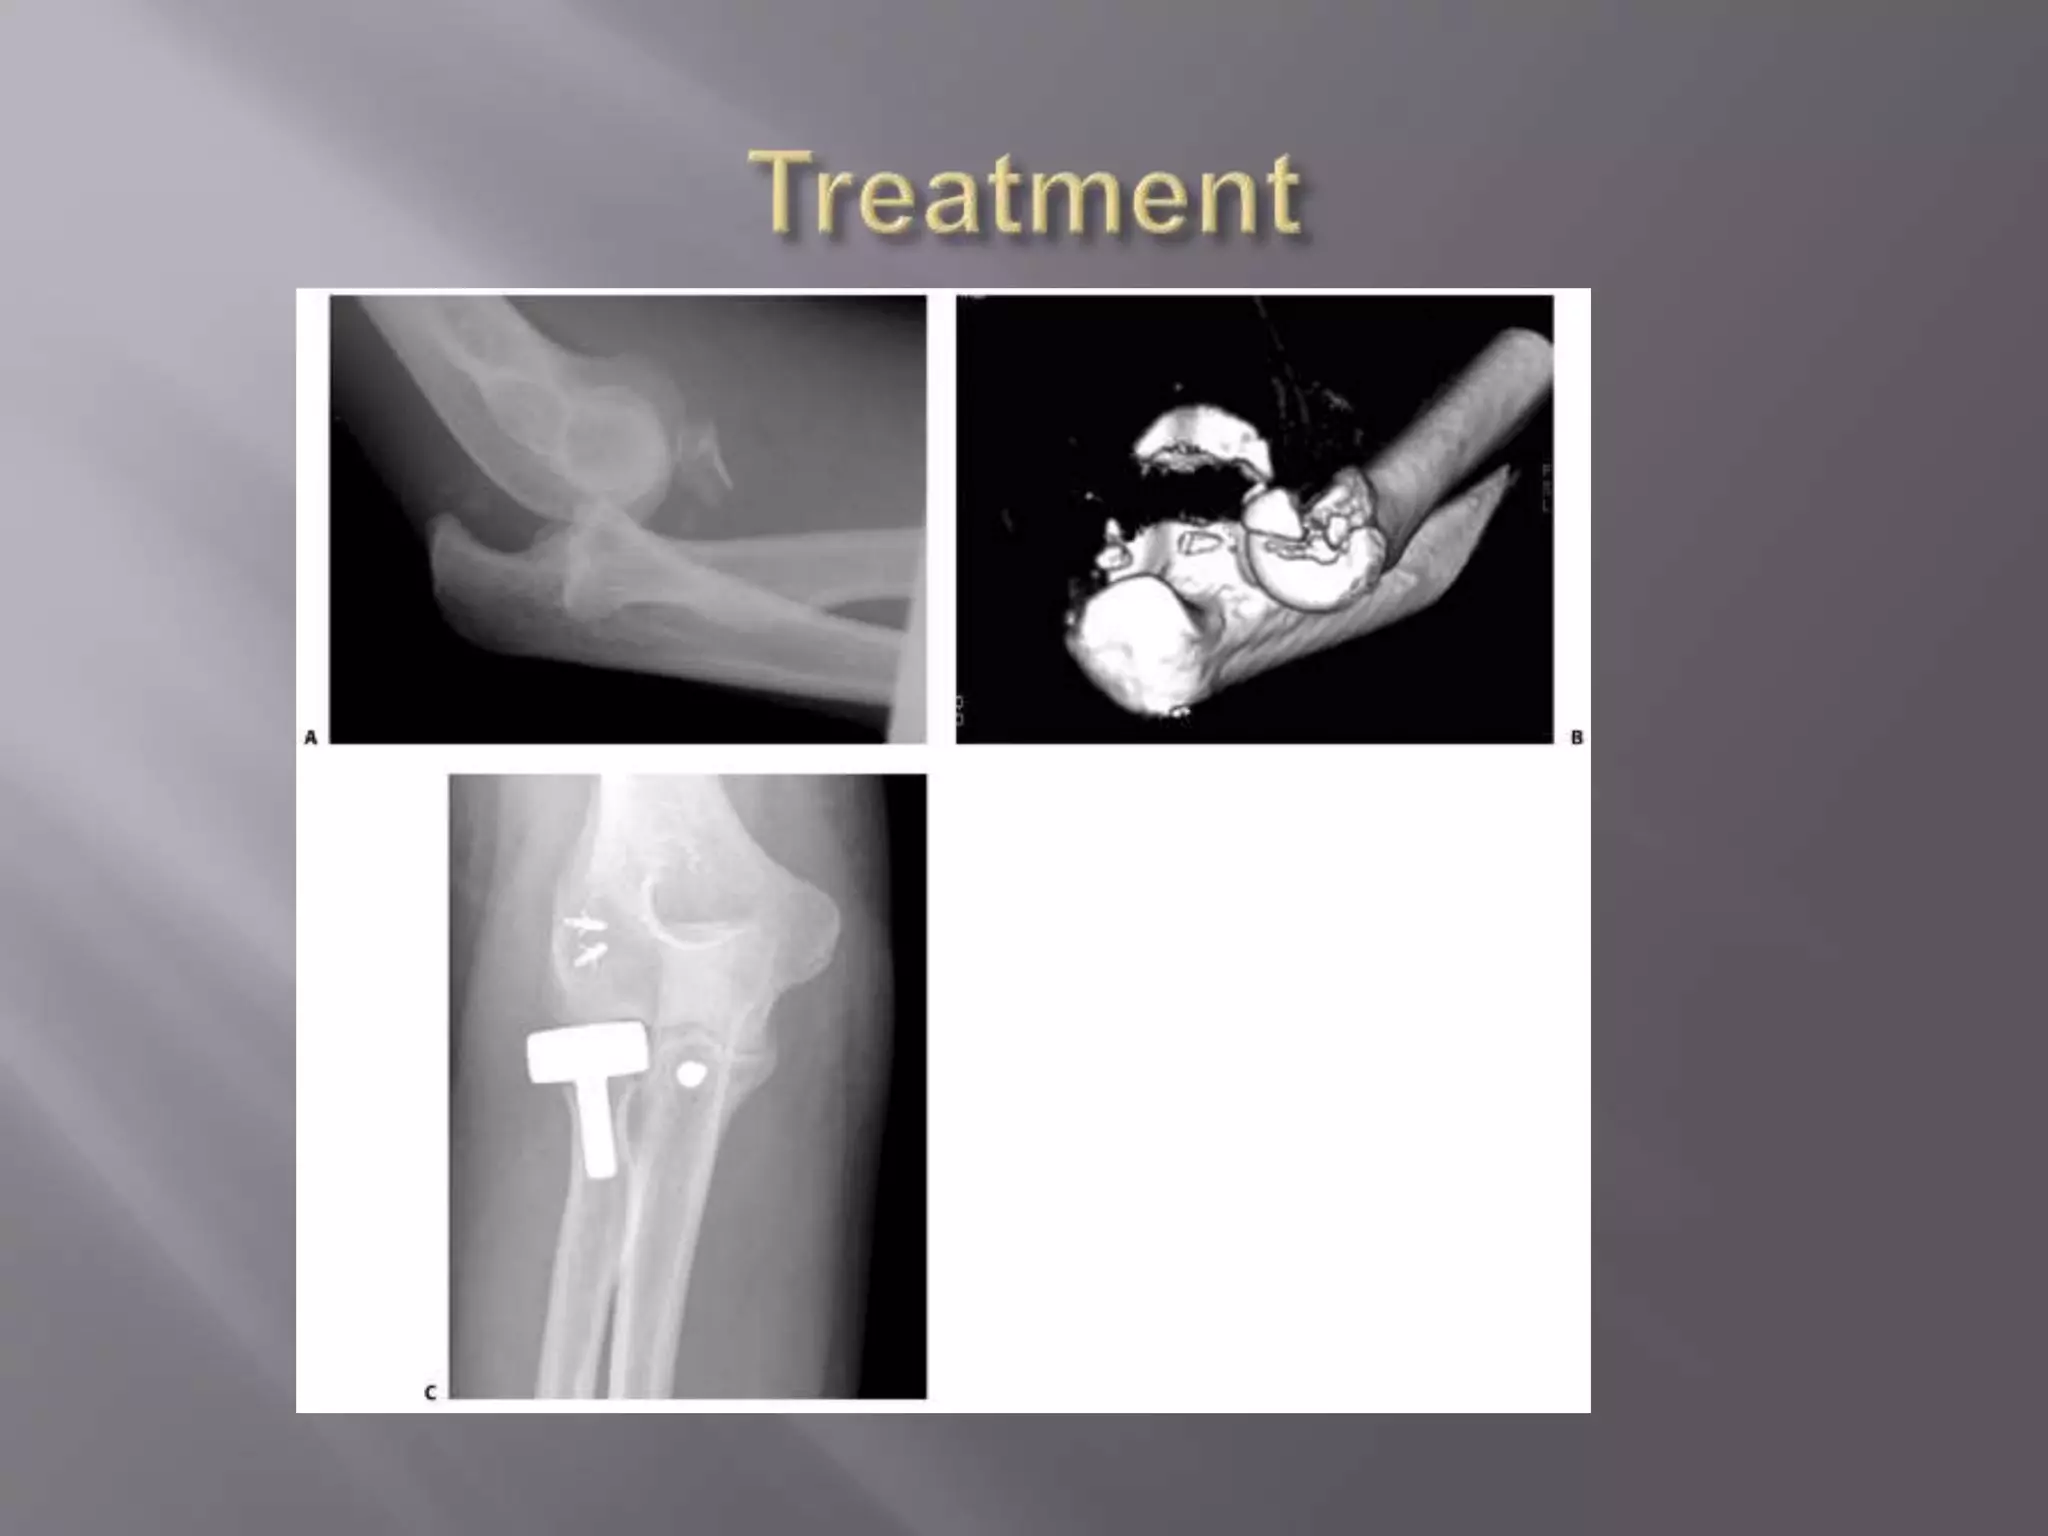

This document discusses the terrible triad injury of the elbow, which involves fractures of the radial head, coronoid process, and posterolateral dislocation. It notes the poor outcomes associated with this injury like stiffness, instability, and hardware failure. The document outlines the relevant anatomy of the medial collateral ligament and lateral uncular collateral ligament. It describes the mechanism of injury, known as the fall on an outstretched hand, and how the ligaments and capsule fail in this injury. Diagnostic imaging and classification of radial head and coronoid fractures are covered. Treatment options including observation, resection, open reduction internal fixation, and replacement are presented. Surgical approaches and techniques are also outlined.